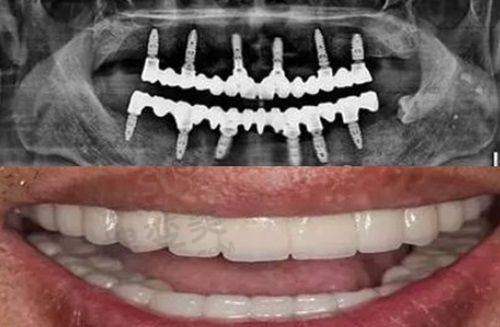

苏州博雅口腔诊所是一家正规的私立口腔诊所。该诊所诊疗项目丰富,涵盖镶牙种植牙、牙齿美白、牙体牙髓、牙周病治疗、牙齿矫正、儿牙等。在特色技术方面,种植牙采用拔尖的 3D 数字化种植导航技术,提升了种植手术成功几率;牙齿矫正采用精良的正矫技术,能有效矫正各种错牙畸形。诊疗环境干净温馨,工作人员热情周到。诊所积极引进国内外精良设备,为诊疗提供了有力支持。医资力量雄厚,邀请国有医院医生坐诊。在当地口碑良好,是众多患者看牙的选择,能为不同需求的患者提供优质的口腔医疗服务。

4、苏州博雅口腔诊所特色项目及技术优势

苏州博雅口腔诊所的特色项目及技术优势显著。其一,种植牙技术堪称行业翘楚,采用 3D 数字化种植导航技术,能有效保护种植体植入位置的精细度,极大提升种植手术成功机率。其二,牙齿矫正技术精良,运用精密的矫治设备和科学的力学原理,可有效矫正各种错牙畸形,为患者塑造良好的牙齿排列和面部曲线。此外,诊所还拥有精良的医疗设备,如 CBCT 机、全景机等,为正确诊断和治疗提供了保护。